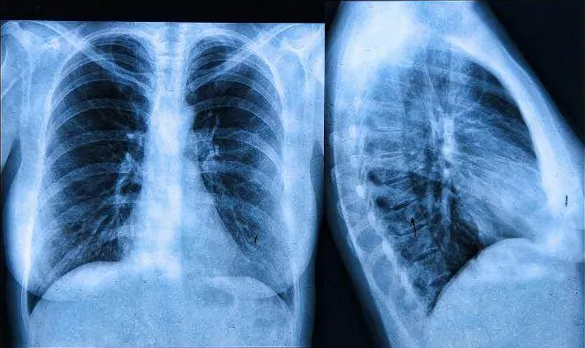

우리나라는 매년 폐암 환자가 2만명 이상 생기고 있다고 합니다. 암 중에서 네번째로 발병률이 높으며 사망은 1위라고 합니다. 폐암의 사망률이 높은 이유는 조기 발견이 되지 않아서인데 모든 병이 그렇듯 조기 발견이 중요한 질병중 하나입니다.

폐암의 생존률은 1기에 발견시 85%, 2기에는 50%, 3기에는 30%, 4기에는 5%이하로 시간이 지날수록 생존률이 낮아지는것을 확인할 수 있습니다. 건강검진에 잘 참여하시고 아래 초기증상도 참고하셔서 건강 챙기시길 바랍니다.